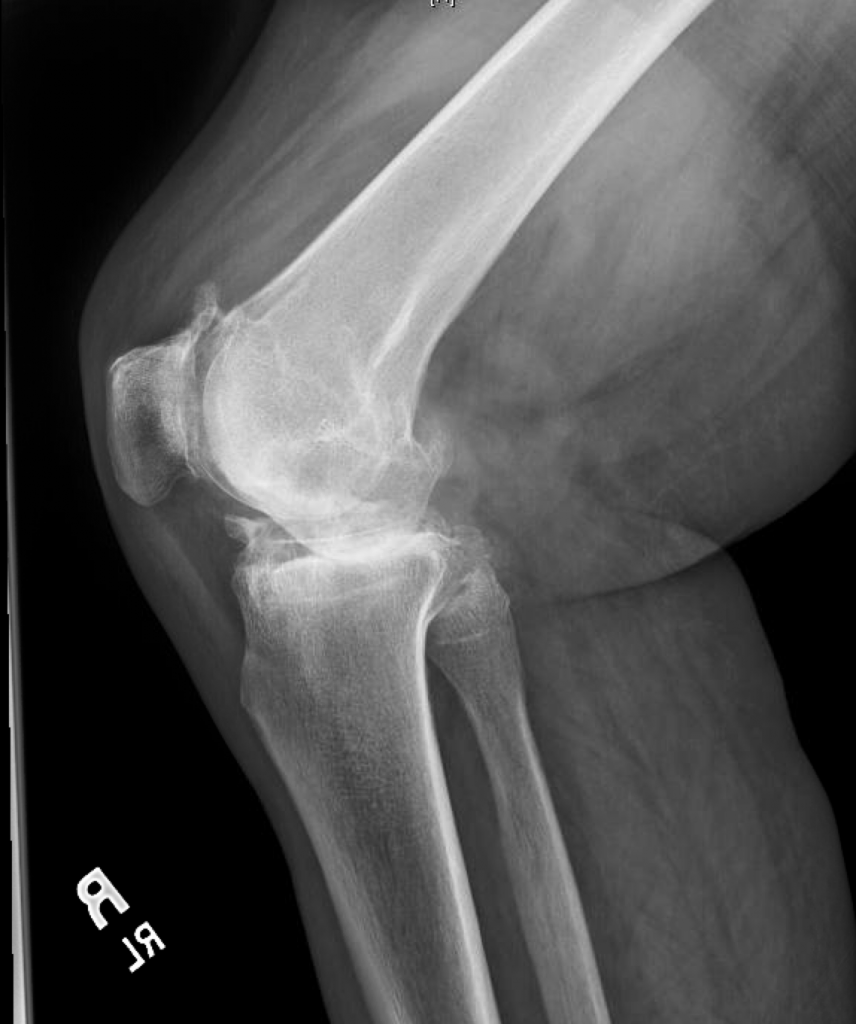

TKA for Severe Valgus Deformity

This is a 75 year old female with end stage arthritis of the right knee and a severe valgus (knock-knee) deformity. She ambulated with a walker and had approximately 25 degrees of valgus with a 15 degree flexion contracture.